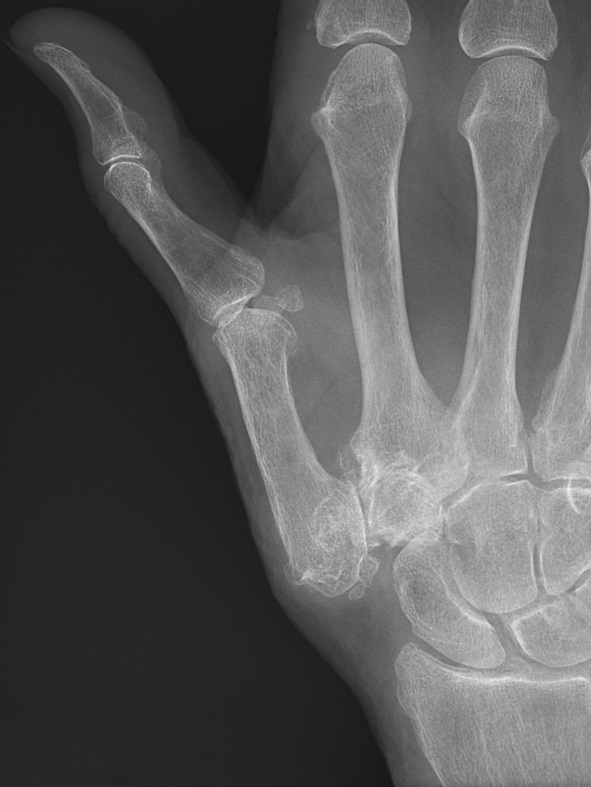

Often plain X-rays can show signs of CMC arthritis. On a plain X-ray, we can see worn cartilage and loss of the space that is normally present between the bones of the joint. We can also see new bone growth which is referred to as bone spurs or osteophytes that result from the bones rubbing against each other.